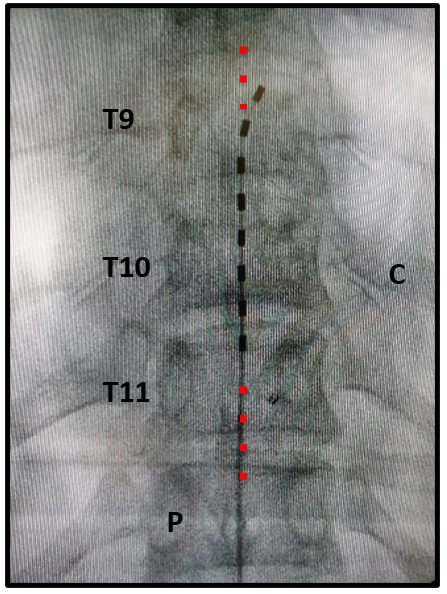

Paso 3. Implantación del electrodo y navegación del espacio epidural. Se introduce el electrodo a través de la aguja y se navega por el espacio epidural hasta colocarlo en el sitio determinado durante la planeación. Se debe verificar la posición del electrodo con proyecciones anteroposteriores y laterales del arco en C mediante fluoroscopia (rayos X). Si se está en la fase de prueba, la posición del electrodo será determinada por la presencia de parestesias que el paciente despierto va a ubicar en la zona del dolor. Si se está en la fase definitiva, la posición del electrodo será determinada por el análisis de la posición del electrodo en la fase de prueba y de los contactos que permitieron una mejoría del dolor (figura 9).

Fuente: fotografía original tomada y modificada por el autor.

Figura 9. Técnica. Paso 3. Navegación epidural con el electrodo de estimulación. Radiografía AP (anteriposterior) donde se observa sobre la línea media un electrodo de estimulación de 8 contactos. Se observa un contacto inferior en el borde superior de T11 y un contacto superior en el borde superior de T9. C: costilla. P: pedículos. La línea roja ilustra la línea media.